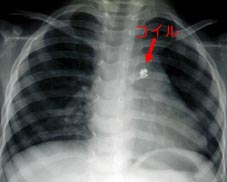

治療後の胸部レントゲン写真

2つのコイルで動脈管を詰めたところ。